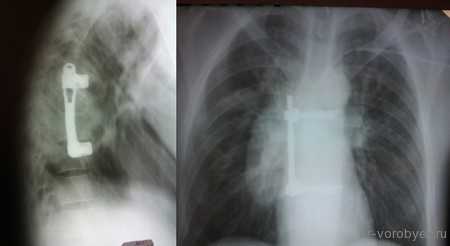

Первым этапом проведена корпорэктомия третьего поясничного позвонка и корпородез МЭШем, заполненным аутокостью

Вторым этапом, с целью создания ротационной стабильности, компрессии позвонков проведена транспедикулярная фиксация.

Пациентка с метастазом в рака молочной железы в первый поясничный позвонок

Выполнена корпорэктомия первого поясничного позвонка и комбинированный корпородез МЭШем и боковой пластиной Centaur фирма Stryker. Наряду с преимуществами, главным из которых является относительная дешевизна данного импланта, МЭШ так же не является идеальной конструкцией для переднего корпородеза и имеет на наш взгляд ряд недостатков: